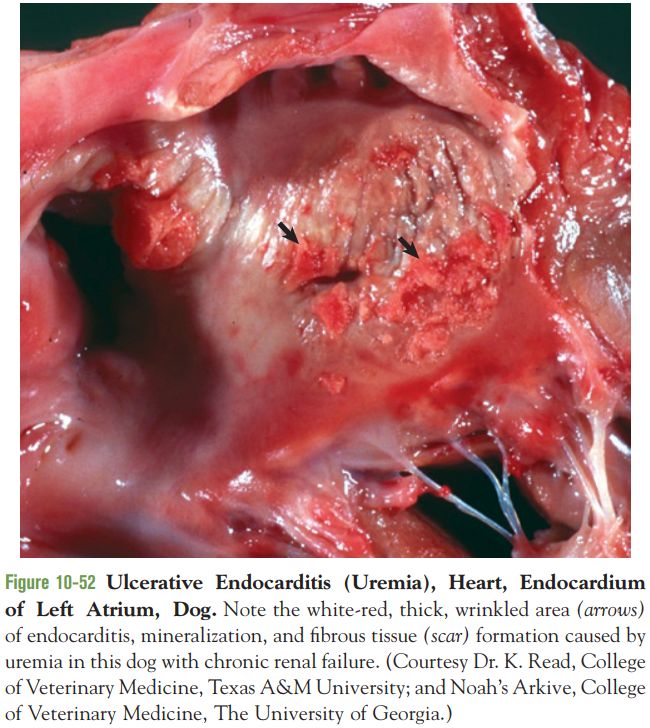

56.下列有關尿毒性心內膜炎之敘述,何者錯誤?

(A)常見於貓

(B)病變區常可見鈣化

(C)病變可能出現心內膜組織壞死及血栓

(D)左心房為主要發病部位